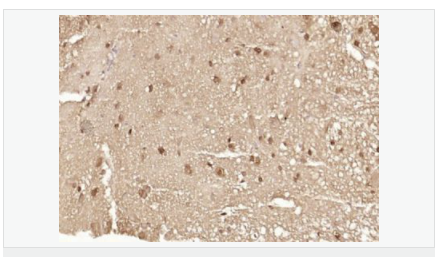

| 产品应用 | ELISA=1:5000-10000 IHC-P=1:100-500 IHC-F=1:100-500 ICC=1:100-500 IF=1:100-500 (石蜡切片需做抗原修复) not yet tested in other applications. optimal dilutions/concentrations should be determined by the end user. |

| 细胞定位 | 细胞核 细胞浆 |

| 产品介绍 | The human ataxin-7 gene, also known as spinocerebellar ataxia 7 or SCA7, maps to chromosome 3p13-p12, has a 2,727-bp open reading frame, and encodes a 892 amino acid protein containing a nuclear localization signal and a polyglutamine tract (1,2). SCA7 is an autosomal dominant neurodegenerative disorder characterized by ataxia and selective neuronal cell loss caused by the expansion of a translated CAG repeat encoding a polyglutamine tract in ataxin-7, which is the SCA7 gene product (3,4). Ataxin-7 is expressed within neurons both affected and unaffected in SCA7 pathology with subcellular localization being variable depending upon the neuronal subtype (5). Polyglutamine expanded in ataxin-7 may carry out its pathogenic effects in the nucleus by altering the matrix-associated nuclear structure and/or by disrupting nucleolar function (6). Function: Ataxin 7 is a protein of unknown function. It may be the human orthologue of the yeast SAGA SGF73 subunit and a subunit of the human TFTC-like transcriptional complexes. Spinocerebellar ataxia 7 (one of a group of hereditary neurodegenrative diseases) is caused by an expanded trinucleotide repeat in the gene encoding ataxin 7. Ataxin 7 is typically located in the cytoplasm and on the nuclear membrane of normal brain neurons. In cells where there is a mutation of the SCA7 gene, ataxin 7 accumulates in intranuclear inclusions and can result in cell death. Subunit: Component of the STAGA transcription coactivator-HAT complex, at least composed of SUPT3H, GCN5L2, TAF5L, TAF6L, SUPT7L, TADA3L, TAD1L, TAF10, TAF12, TRRAP, TAF9 and ATXN7. The STAGA core complex is associated with a subcomplex required for histone deubiquitination composed of ATXN7L3, ENY2 and USP22. Interacts with SORBS1, PSMC1 and CRX. Interacts with TRRAP, GCN5L2 and TAF10. Interacts with alpha tubulin. Subcellular Location: Cytoplasmic (isoform b) and Nuclear (isoform a) Tissue Specificity: Isoform a and isoform b are expressed in CNS, but isoform a is expressed predominantly in the peripherical tissues. Isoform b is also highly expressed in the frontal lobe, skeletal muscle and spinal cord and is expressed at a lower level in the lung, lymphoblast and intestine. Post-translational modifications: Proteolytically cleaved. The cleavage may be involved in SCA7 degeneration: the isoform fragments may exert distinct toxic influences that could contribute to selective neurodegeneration. Sumoylation decreases the aggregation propensity and cellular toxicity of forms with an expanded poly-Gln region but has no effect on subcellular location or interaction with components of the STAGA complex. DISEASE: Defects in ATXN7 are the cause of spinocerebellar ataxia type 7 (SCA7) [MIM:164500]; also known as olivopontocerebellar atrophy III (OPCA III or OPCA3) or olivopontocerebellar atrophy with retinal degeneration. Spinocerebellar ataxia is a clinically and genetically heterogeneous group of cerebellar disorders. Patients show progressive incoordination of gait and often poor coordination of hands, speech and eye movements, due to degeneration of the cerebellum with variable involvement of the brainstem and spinal cord. SCA7 belongs to the autosomal dominant cerebellar ataxias type II (ADCA II) which are characterized by cerebellar ataxia with retinal degeneration and pigmentary macular dystrophy. Similarity: Belongs to the ataxin-7 family. Contains 1 SCA7 domain. SWISS: O15265 Gene ID: 6314 Database links: Entrez Gene: 6314 Human Entrez Gene: 246103 Mouse Omim: 164500 Human Omim: 607640 Human SwissProt: O15265 Human SwissProt: Q8R4I1 Mouse Unigene: 476595 Human Important Note: This product as supplied is intended for research use only, not for use in human, therapeutic or diagnostic applications. |